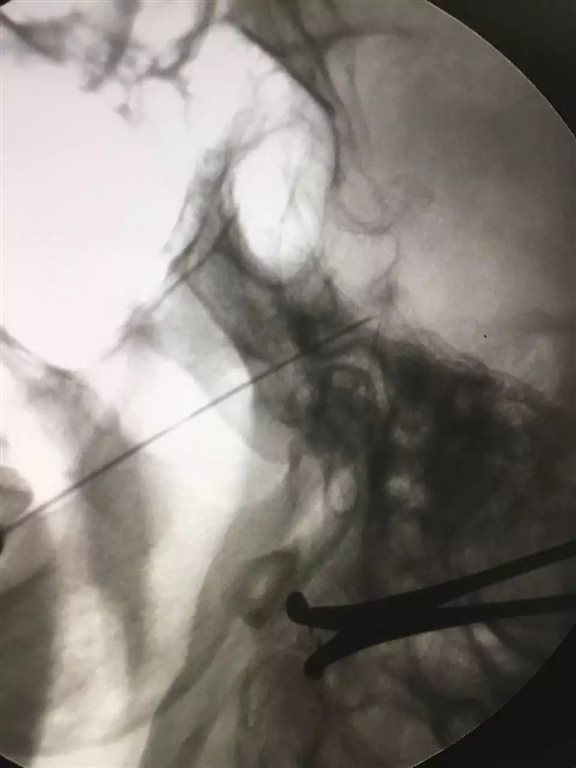

置入测试电极,0.3V 50HZ感觉测试引出第二支异感,注入无水乙醇0.2ml,

调整测试电极,0.3V 50HZ感觉测试引出第三支异感,运动测试0.7V 2HZ未引出咬肌收缩,注入无水乙醇0.3ml

反复测试三叉神经第二和第三支痛觉完全消失。

虽然术中穿刺针到达半月神经节时,由于迷走神经反射,一度心率从90次瞬间降到了47次,好在有惊无险,停止操作后逐步恢复正常,算是第三个变数吧,不过,看着老太太满意的表情,出去吃饭的时候护士们说我是这样摇着出去的......